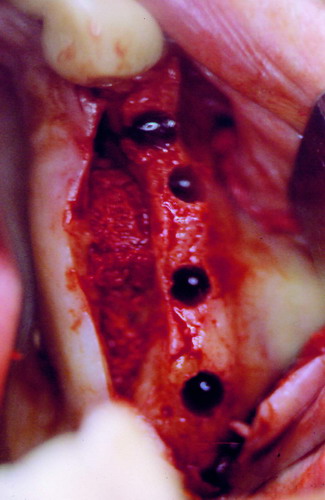

LA OCLUSIÓN MUTUAMENTE PROTEGIDA ES UN VIEJO CONCEPTO QUE CONSISTE EN LA MUTUA INTERACCIÓN DE LOS DISTINTOS GRUPOS DENTARIOS ENTRE SI. DE ESTA FORMA, LA TABLA PREMOLAR / MOLAR DE AMBOS HEMIMAXILARES ANTAGONISTAS, DETIENEN EL CIERRE MANDIBULAR EN CÉNTRICA, LOS CANINOS DISCLUYEN LAS PIEZAS POSTERIORES DURANTE LAS TRANSTRUSIONES, Y EL GRUPO INCISIVO LO MISMO DURANTE LAS PROPULSIVAS. SIN EMBARGO, DICHO CONCEPTO ES LIMITADO A LAS PIEZAS DENTARIAS, SIN TENER EN CONSIDERACIÓN LA IMPORTANTE FUNCIÓN QUE RECAE SOBRE LA ATM Y EN EL SOPORTE DE PRESIONES DURANTE ESTA DINÁMICA. ES ASI QUE EN EL AÑO 1981, EL DR. ANIBAL ALONSO GENERA EN LA CIUDAD DE BUENOS AIRES UN CONCEPTO MAS AMPLIO QUE DENOMINÓ : OCLUSION MUTUAMENTE COMPARTIDA. REF I EN EL QUE AMPLÍA EL CONCEPTO ANTERIOR, HACIENDO PARTÍCIPE A LA ATM EN LA MISMA. CUANDO EXISTE CARENCIA DE PIEZAS DENTARIAS POSTERIORES, YA SEA DE UN SOLO LADO O DE AMBOS , EL CIERRE MANDIBULAR ES DETENIDO POR LAS PIEZAS RESTANTE, FORZANDO A LA ATM A SOPORTAR PRESIONES MUY SUPERIORES A AQUELLAS PARA LAS QUE ESTA PREPARADA. FIG1 FIG2 FIG3 LUEGO DEL ESTUDIO CLÍNICO DE RIGOR, DONDE SE EVALÚA RADIOGRÁFICA Y PERIODONTALMENTE, SE PROCEDE A TOMAR MODELOS DE ESTUDIO Y MONTAR EN ARTICULADOR SEMIAJUSTABLE, SOBRE EL CUAL SE REALIZA UN ENCERADO PROGRESIVO DE DIAGNÓSTICO, A PARTIR DEL CUAL SE CONFECCIONA UN JUEGO COMPLETO DE PROVISIONALES DE AMBAS ARCADAS , INCLUYENDO LAS PIEZAS FALTANTES. SE ABORDA EL CASO YA QUIRÚRGICAMENTE DONDE EN UNA PRIMERA ETAPA SE TALLAN PRIMARIAMENTE LAS PIEZAS DENTARIAS Y SE PROCEDE, EXODONCIANDO EL INCISIVO CENTRAL SUPERIOR DERECHO, A REALIZAR UNA ROG(REGENERACIÓN ÓSEA GUIADA), PARA INMEDIATAMENTE INSTALAR PARTE DE NUESTROS PROVISORIOS EN LA GUIA ANTERIOR. SE ADAPTAN A LOS SECTORES POSTERIORES LAS PRÓTESIS REMOVIBLES QUE PORTABA, Y SE ESPERAN CUATRO MESES, AL CABO DE LOS CUALES SE REALIZA UN ESTUDIO CON DENTASCAN, MEDIANTE EL USO DE UNA FÉRULA RADIOLÓGICA CON TUBOS METÁLICOS , QUE NOS SERVIRÁ TAMBIÉN DE GUÍA QUIRÚRGICA. PROCEDEMOS ENTONCES A LA IMPLANTACIÓN DE LOS SECTORES EDÉNTULOS MEDIANTE IMPLANTES ROSCADOS Y TÉCNICA SEMI SUMERGIDA. TRANSCURRIDAS OCHO SEMANAS OBSERVAMOS UNA CORRECTA SALUD PERIMPLANTARIA, Y REALIZAMOS LA INSTALACIÓN DE LOS ABUTTMENTS ALCANZAMOS ENTONCES EL PUNTO EXACTO DONDE DEBEREMOS COMENZAR A RECONTRUIR EN FORMA PERMANENTE. PAZ DEL SISTEMA: CENTRICIDADARTICULAR-PAZ MUSCULAR-ESTABILIDAD- -ACOPLAMIENTO. BASES FUNDAMENTALES DE LA OCLUSIÓN ORGÁNICA FIG41 FIG42 PROCEDEMOS NUEVAMENTE A TOMAR IMPRESIONES, EN ESTE CASO DEFINITIVAS , MONTAR NUEVAMENTE EN ARTICULADOR, Y CONSTRUIR LAS RESTAURACIONES PERIFÉRICAS TOTALES EN BASE A PORCELANA SOBRE ORO GALVANIZADO. REF. II SOBRE LAS MISMAS TERMINADAS Y YA EN BOCA, CHEQUEÁMOS TODOS LOS ELEMENTOS QUE CONSTITUYEN UNA REHABILITACIÓN ORAL INTEGRAL, DESDE LA SALUD ENDODONTICA DE PIEZAS TRATADAS O NO, LA SALUD PERIODONTAL, EL AJUSTE PERIFÉRICO DE LAS RESTAURACIONES, LA ESTABILIDAD EN LA ATM, Y LAS FUNCIONES OCLUSALES, CHEQUEOS ESTOS QUE SE REPETIRAN EN CADA UNO DE LOS CONTROLES POST OPERATORIOS. FIG46 FIG47 FIG48 FIG66 FIG67 REFERENCIAS: REF I: OCLUSIÓN Y DIAGNÓSTICO EN REHABILITACIÓN ORAL REF. II ELECTROFORMACIÓN EN ODONTOLOGÍA RESTAURADORA.